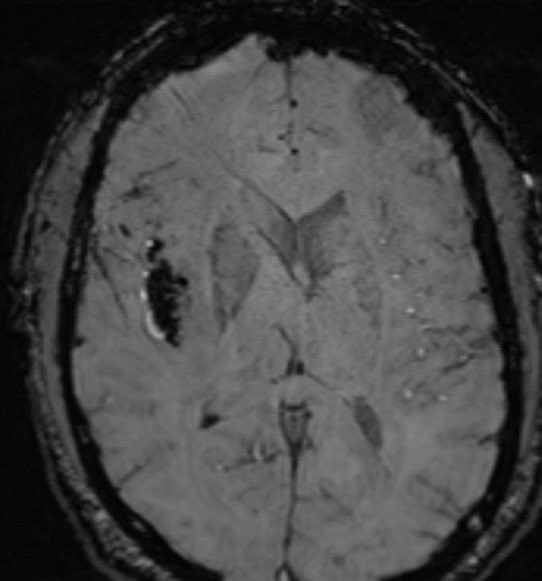

ROC of the week: Herpes encephalitis Findings: confluent FLAIR hyper intense signal involving the right temporal lobe, insula and subgenual cingulate with associated susceptibility artifact

#FOAMrad#FOAMmed#radres#neurorad#radiologypic.twitter.com/4BMDiCf5pF